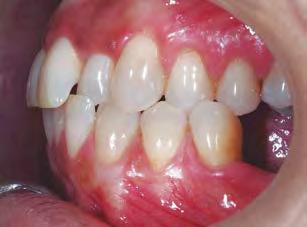

–MARPE, una alternativa a la disyunción en el paciente adulto, por el Dr. Enrique Solano y cols. [88]